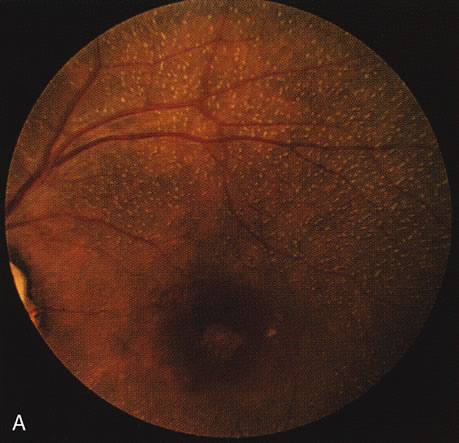

In retinitis pigmentosa (RP), the pigment abnormalities of atrophy, migration, and clumping are made apparent by transmitted hyperfluorescence and blocked hypofluorescence (Fig. 1A). Patients who have very minimal pigmentary alterations (pauci pigmentary RP) or no pigment abnormalities (RP sine pigmento) may show the abnormalities on fluorescien angiography (FA). It is uncommon to see choriocapillaris atrophy except in the late stages. This finding corresponds to the histopathology, which shows that the earliest abnormalities are in the photoreceptors and that the choroid is normal.1

Fig. 1. Retinitis pigmentosa. A. A typical area of bone spicule pigmentation. B. Diffuse dye leakage is apparent throughout the posterior pole. C. The early angiogram shows dilated and irregular retinal radial peripapillary capillaries and perifoveal retinal capillaries. D. Leakage from these vessels are evident in the late angiogram.

Dye leakage in RP may occur from the retinal vessels or at the level of the retinal pigment epithelium (Fig. 1B).2–4 The leakage may be seen in the macula and posterior pole, along the vascular arcades in the distribution of the radial peripapillary capillaries, and in the periphery (where an exudative vasculopathy resembling Coats' disease is suggested).

Of more clinical importance is the role of FA in the diagnosis and treatment of cystoid macular edema (CME) (Fig. 1C and D). Stereoscopic FA indicates that the leakage, which may be diffuse or have the typical petaloid stellate appearance of CME, can come from the perifoveal retinal capillaries, from the choroid through the RPE, or from a combination of both sources.4 With the recent suggestion that CME in RP may be successfully treated with acetazolamide,5, 6 FA is thus important to document the diagnosis of CME, establish the origin(s) of leakage, and follow patients during and after therapy.